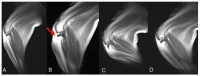

Kinematic MRI (kMRI) is a novel human imaging technique that couples the excellent soft tissue contrast and multiplanar capabilities of traditional MRI with kinematic potential. The study's goals are: (1) testing the feasibility of spinal cord and joints real-time kMRI; and (2) evaluating the quality of these kinematic studies as a new diagnostic option in veterinary medicine. Standard and real-time kinematic MRI were performed on cervical spine, elbow, and stifle joints of seven cadavers. Studies were repeated after a surgical insult aimed to create a certain degree of joint instability. A total of 56 MRI were performed-7 cervical spinal tracts, 3 elbow joints, and 4 stifle joints were examined. The technique was feasible in all the three regions examined. The images were considered of excellent quality for the stifle joint, good to fair for the cervical spine, whereas two of three elbow studies were considered to have unacceptable image quality. Additionally, real-time kMRI provided good to excellent information about stifle instability. Therefore we consider kMRI a promising technique in veterinary medicine. Further studies and an in vivo setting are needed to increase the quality of the kMRI images, and to fully evaluate clinical usefulness.